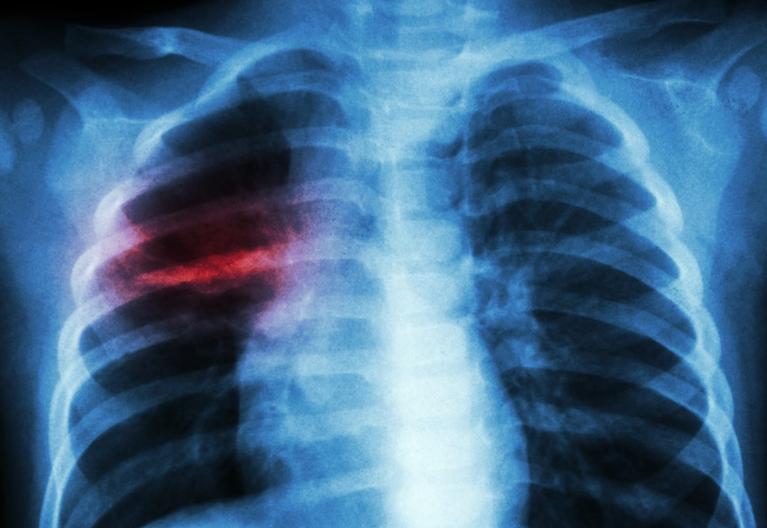

在小儿肺炎恢复期时肺泡腔内渗出液并未完全排出,病原微生物产生的毒素或代谢产物也未完全排出体外,刺激气道黏膜,使其充血、水肿,管道狭窄。

儿童由于气管、支气管较成人狭长, 管腔缺乏弹力, 黏膜纤毛运动性差,肺泡弹性差,加上神经系统、大脑皮层发育不完善,咳嗽反射较弱,主动咳嗽较少。因此,排痰不畅、痰液淤滞、气道堵塞。

在肺炎的急性期时,肺部急性渗出性炎症将由各种原因引起,肺泡壁毛细血管弥漫性扩张充血,并且肺泡内充满大量渗出液。

进行对症治疗后,在恢复期微血管仍存在红细胞及血小板聚集,阻碍了肺泡恢复正常的生理组织结构,出现了肺部微循环障碍,导致肺部通气不足和换气障碍。